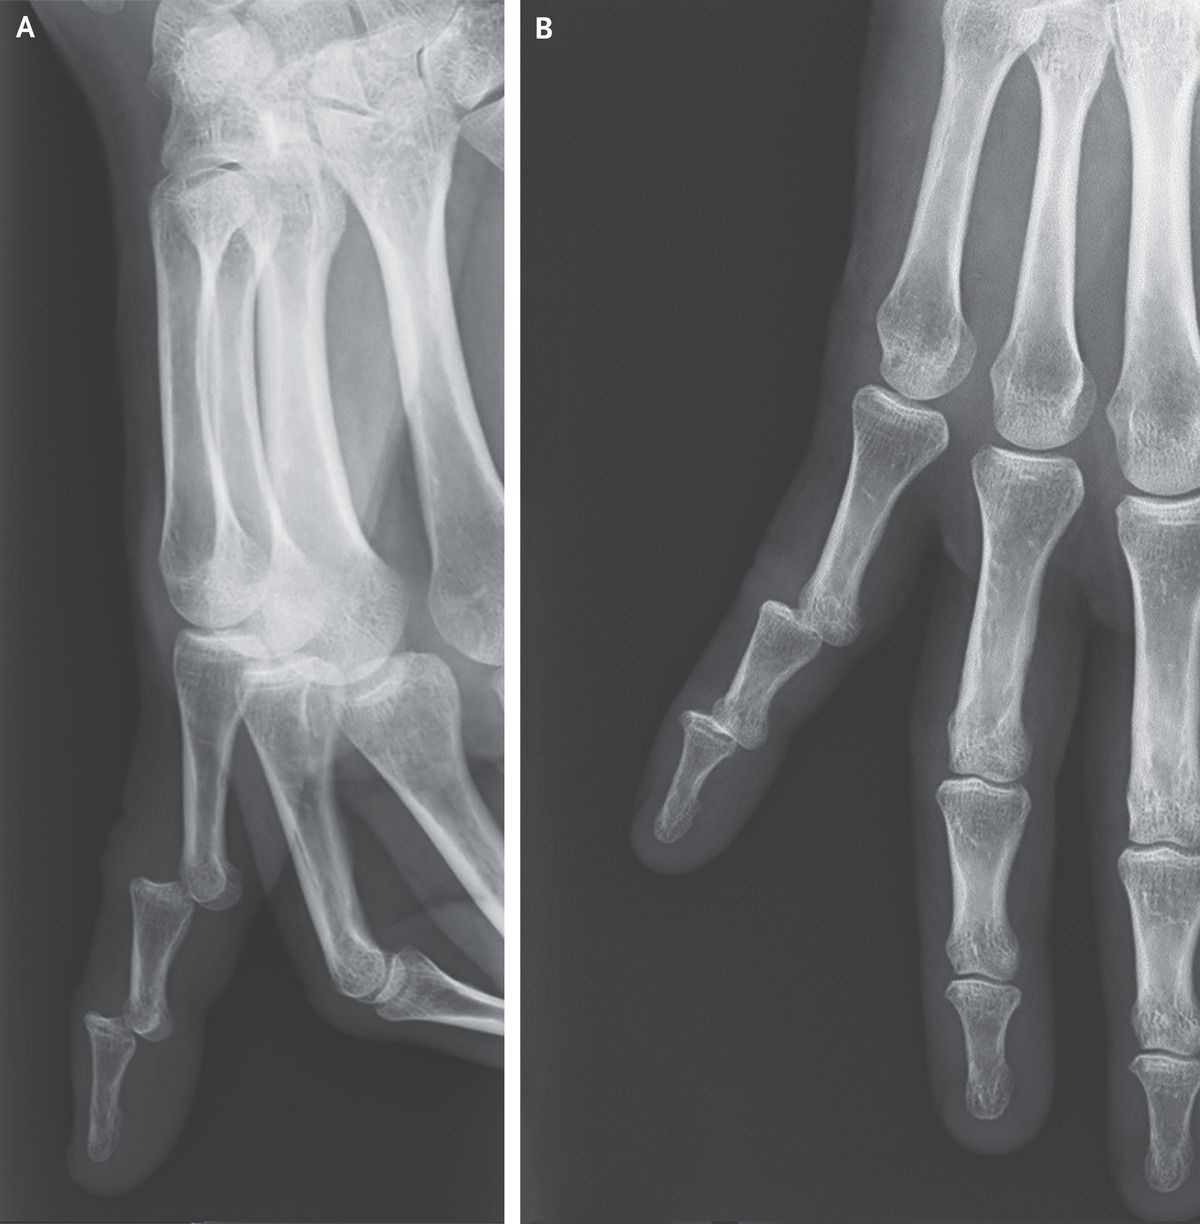

A 54-year-old woman presented to the emergency department with a crooked, painful finger after she had fallen backward onto her outstretched hand 1 hour earlier. On physical examination, dorsal displacement of the right fifth (“pinky”) finger was noted at the proximal and distal interphalangeal joints. The patient was unable to move the finger. There were no signs of neurovascular compromise. Radiographs of the right hand showed dorsal dislocation of the proximal and distal interphalangeal joints of the fifth finger, which created a “stepladder” shape (Panel A, lateral view; Panel B, posteroanterior view). A diagnosis of simultaneous dislocation of the proximal and distal interphalangeal joints of the fifth finger was made. Although dislocation of an interphalangeal joint is commonly seen, simultaneous dislocations within the same finger are rare. Treatment with closed reduction and splinting of the finger was provided. Three weeks after reduction, the splint was removed and the patient was counseled to resume an active range of motion with the finger without weight-bearing for 4 additional weeks. At the 6-month follow-up, the patient had full function of the finger.